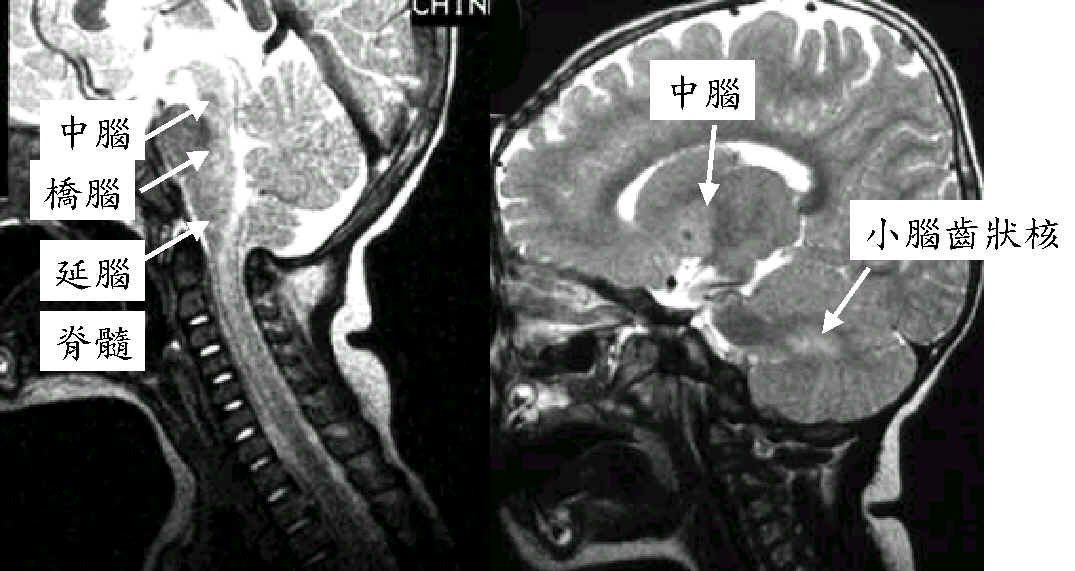

2歲女孩,手足口疾病合併腦炎

腦炎侵犯

中腦的中央及後面

橋腦的後及腦齒狀核

腦炎更往下

侵犯脊髓

中腦的中央及橋腦、延腦的後面及小腦齒狀核,

更往下侵犯脊髓